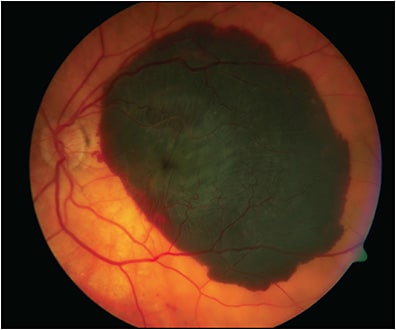

Finally, Optos (Optos Inc) is a noncontact SLO that can image up to 200° of the retina, or 82% of retinal surface area. Notably, it can acquire this image even through a nonmydriatic pupil by using ellipsoid mirror and virtual point technology.1 In addition to fundus photography, it can capture FFA, FAF (green), and ICGA images. Patients can be imaged sitting up or in the “flying baby” position in cases of retinopathy of prematurity (ROP) screening.14 Optos has the widest field of view in a single click of all existing cameras and does not require pupillary dilation, but its pseudocolor image can make it more difficult to detect the true coloration of retina, which can be problematic in imaging pathologies such as choroidal nevi.10 The composite image in Figure 3 shows how a variety of peripheral retinal pathologies would appear when captured on an UWF image.

Multimodal UWF imaging is now widely used in ophthalmology clinics, especially in retina practices. Its numerous advantages include fast image acquisition time and simultaneous high-quality imaging of both the central and peripheral retina. Ultrawidefield imaging can aid in the diagnosis and management of both posterior and peripheral chorioretinal pathologies, including retinal vascular diseases (eg, diabetic retinopathy, venous or arterial occlusions, vasculitis) (Figure 4); age-related macular degeneration; retinal detachments (RD) (Figure 5); or peripheral retinal degenerations (eg, holes, lattice, retinoschisis); neoplastic lesions (primary malignancies or metastases); infectious and noninfectious posterior uveitis (Figure 6); hereditary chorioretinal dystrophies (Figure 7); and various pediatric vitreoretinal disorders such as ROP or familial exudative vitreoretinopathy.1,15 In addition, UWF imaging can monitor disease progression over time, provide patient education by helping patients visualize their own disease, and become an invaluable tool in telemedicine screening for diseases such as diabetic retinopathy.16